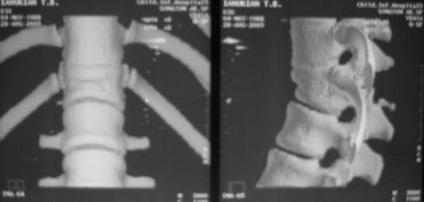

multiple hernii

Găsirea mai multor defecte uzuratsii (ca radiologi descrise SHmorlja hernia) este un semn indirect al patologiei Scheuermann, care este o astfel de boala degenerativă grea, care este format din motive necunoscute, adolescenți, caracterizate prin dezvoltarea cifozei toracice progresive, gipolordoza lombare.

Alte cauze includ cartilagiu predispozitia genetica si tesutul osos al coloanei vertebrale, lipsa de calciu în organism.

Aceste hernii sunt adesea cauza tulburărilor motorii ale capacității coloanei vertebrale, pot fi asimptomatice.

Foto: multiple SHmorlja hernie

In unele cazuri, a descoperit accidental adolescent multiple hernii poate să dispară în mod independent de maturitate.